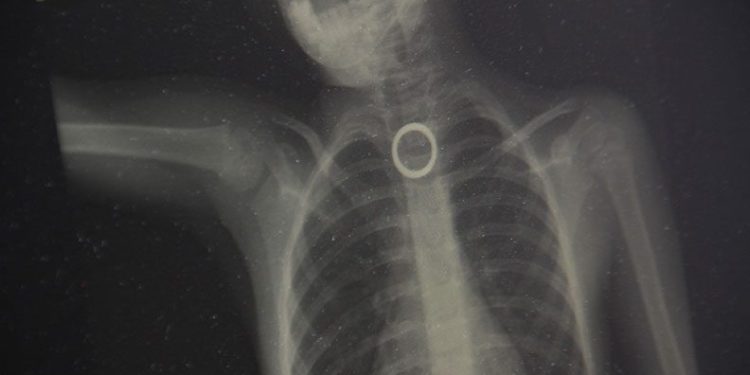

Elazığ’da evde oyun oynayan 3 yaşındaki çocuk, yakınında bulunan yüzüğü yuttu. Durumu fark eden ebeveynler çocuğu hemen Fırat Üniversitesi Hastanesine getirerek Çocuk Gastroenteroloji Ana Bilim Dalı Başkanı Prof. Dr. Yaşar Doğan’a gösterdi. Burada yapılan tetkiklerde yutulan yüzüğün yemek borusu birinci darlık kısmında takılı kaldığı görüldü. Hemen Çocuk Endoskopi Ünitesine alınan 3 yaşındaki çocuğun boğazındaki yüzük yapılan endoskopik yöntemle çıkartıldı. Sağlık durumu iyi olan çocuk taburcu edilirken, uyarılarda bulunan Çocuk Gastroenteroloji Ana Bilim Dalı Başkanı Yaşar Doğan, bu tür vakaların meydana gelmemesi için ailelerin, çocukların etrafından bulunan yabancı cisimleri uzaklaştırmaları gerektiğini belirtti.

Hastanın 3 yaşında olduğunu belirten Çocuk Gastroenteroloji Ana Bilim Dalı Başkanı Prof. Dr. Yaşar Doğan, “Bu hastamız akşam saatlerinde boğazına yabancı cisim yutma yakınmasıyla ailesi tarafından hastanemize getirildi. Yaptığımız incelemeler neticesinde özellikle yemek borusunun birinci darlık kısmında yüzüğü benzer bir yabancı cisim gördük. İlk geldiğinde hasta yeni beslendiğinden dolayı endoskopi için açlık süresi bekletildi. Ondan sonra gerekli olan endoskopi işlem yapılarak oradaki yabancı cisim çıkartıldı. Çıkarma işlemi başarılı bir şekilde yapıldıktan sonra aile 2 saatlik gözlemden sonra evine gönderildi. Şu anda herhangi bir sıkıntısı yok.